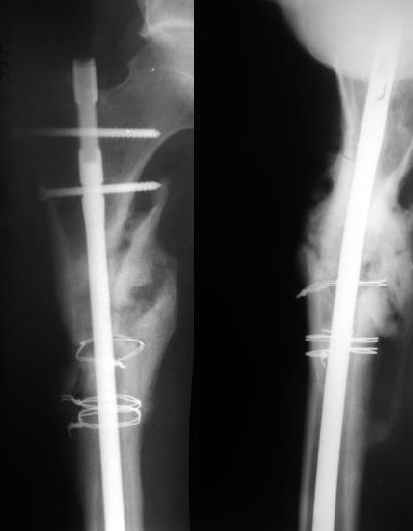

Еще один пример - несращение через полгода после несостоятельного остеосинтеза, и через полгода после реостеосинтеза с блокированием.

1

2